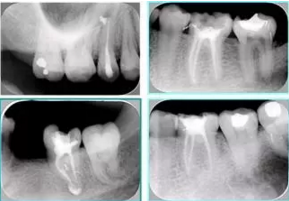

共有 4 張 X 線片,分別是術(shù)前、診斷絲 、主牙膠尖確認(rèn)、術(shù)后。

( 1 )術(shù)前:術(shù)前 X 線片用來了解牙齒的大概情況。術(shù)前預(yù)期為多根牙時 X 線片應(yīng)偏頭拍攝。

( 2 )診斷絲:根據(jù)術(shù)前 X 線片進(jìn)行開髓、根管的初步預(yù)備后,需要插入診斷絲,用來指示工作器械位置。常用 10 號或 15 號擴(kuò)大器作為診斷絲插入牙髓腔。

( 3 )主牙膠尖確認(rèn):通過術(shù)前預(yù)期和診斷絲診斷,明確工作長度、牙根走向,進(jìn)行根管預(yù)備。之后應(yīng)進(jìn)行主牙膠尖(中銼)確認(rèn),已明確根管是否適合充填。

( 4 )術(shù)后:觀察治療效果。

術(shù)后 X 線片用來評定根管充填 長度、致密度(管壁清晰、側(cè)枝)等指標(biāo)。

圖為根管充填術(shù)后 X 線片。圖中可見,根管充填較好。右下圖有白色小點(diǎn),為側(cè)方加壓導(dǎo)致糊劑擠出所致,表明根管充填比較致密。

多根牙時候需進(jìn)行偏移投照,正位投照無法說明具體哪根牙根管充填效果。